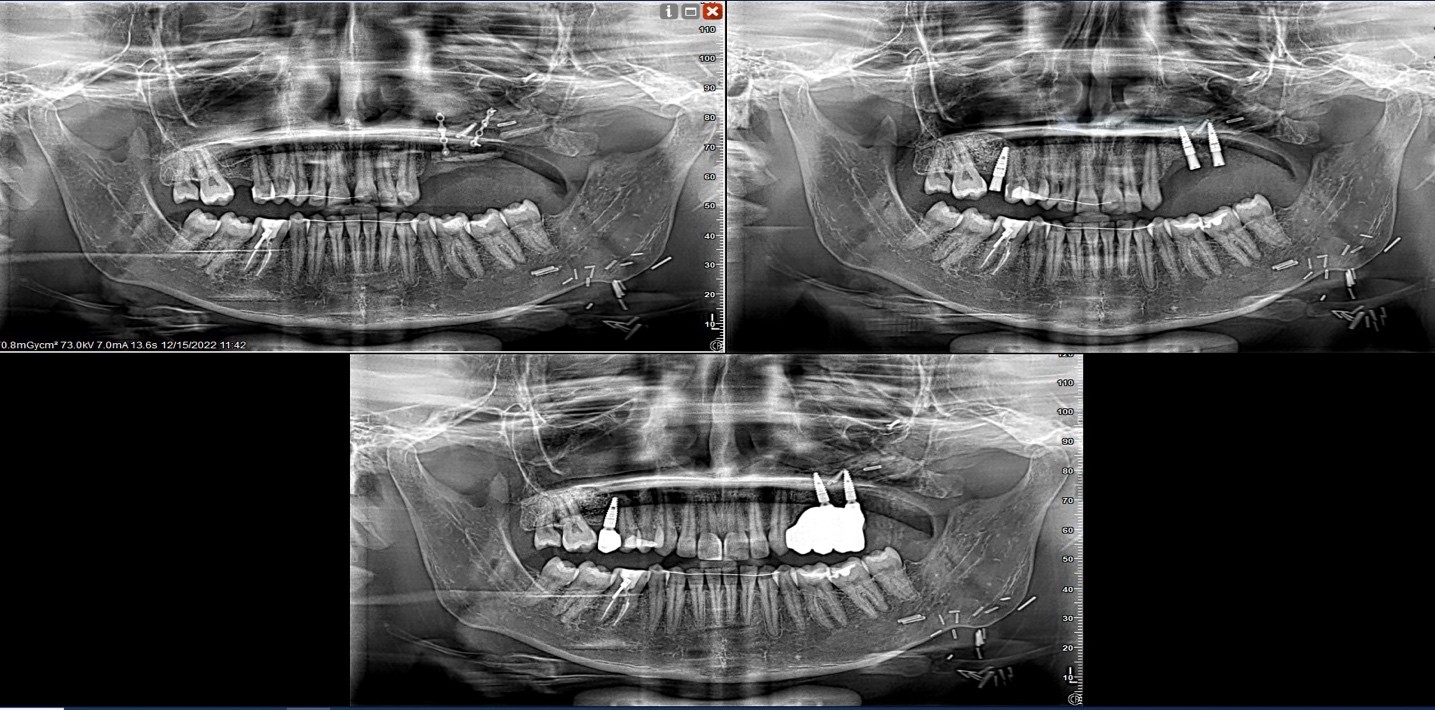

A distraction device was placed after a latency period of 7 days. The fibula graft underwent vertical distraction over a 6-week period at a rate of 0.5 mm twice daily, achieving approximately 12 mm of vertical bone gain. Radiographic evaluation (Image 1 and 2) showed successful osteogenesis without complications. After a 3-month consolidation period, dental implants were placed into the distracted fibula segment.

Clinical and radiographic images comprehensively demonstrate the sequential stages of surgical reconstruction and prosthetic rehabilitation. The newly added distraction phase X-ray (Image 2a) illustrates the fibula graft with an attached vertical distraction device in situ. This image confirms the mechanical application of distraction osteogenesis, clearly showing the distractor's position and alignment with the maxillary segment. It follows the initial pre-distraction radiograph (Image 1), where the fibula graft is secured with titanium plates after maxillary resection.

Following distraction, the post-distraction radiograph (Image 2b) reveals successful vertical bone elongation. The post-implant and prosthesis image (Image 3) further demonstrates ideal implant placement and successful prosthetic integration. Intraoral photographs (Images 4 and 5) depict the final fixed prosthesis with harmonious gingival contours and alignment, while the frontal occlusion view (Image 6) confirms esthetic and functional restoration. The entire workflow from device installation to final rehabilitation is supported by radiographic and clinical validation.

1.Post-distraction Radiograph: Evident vertical bone gain following distraction osteogenesis.

2. Post-implant Radiograph: Stable implant integration with prosthetic adaptation.

Fig 3: Panoramic radiograph showing vertical distraction device in situ over fibula free flap. The distractor is clearly visualized, demonstrating its alignment and integration with the grafted segment for vertical osteogenesis.